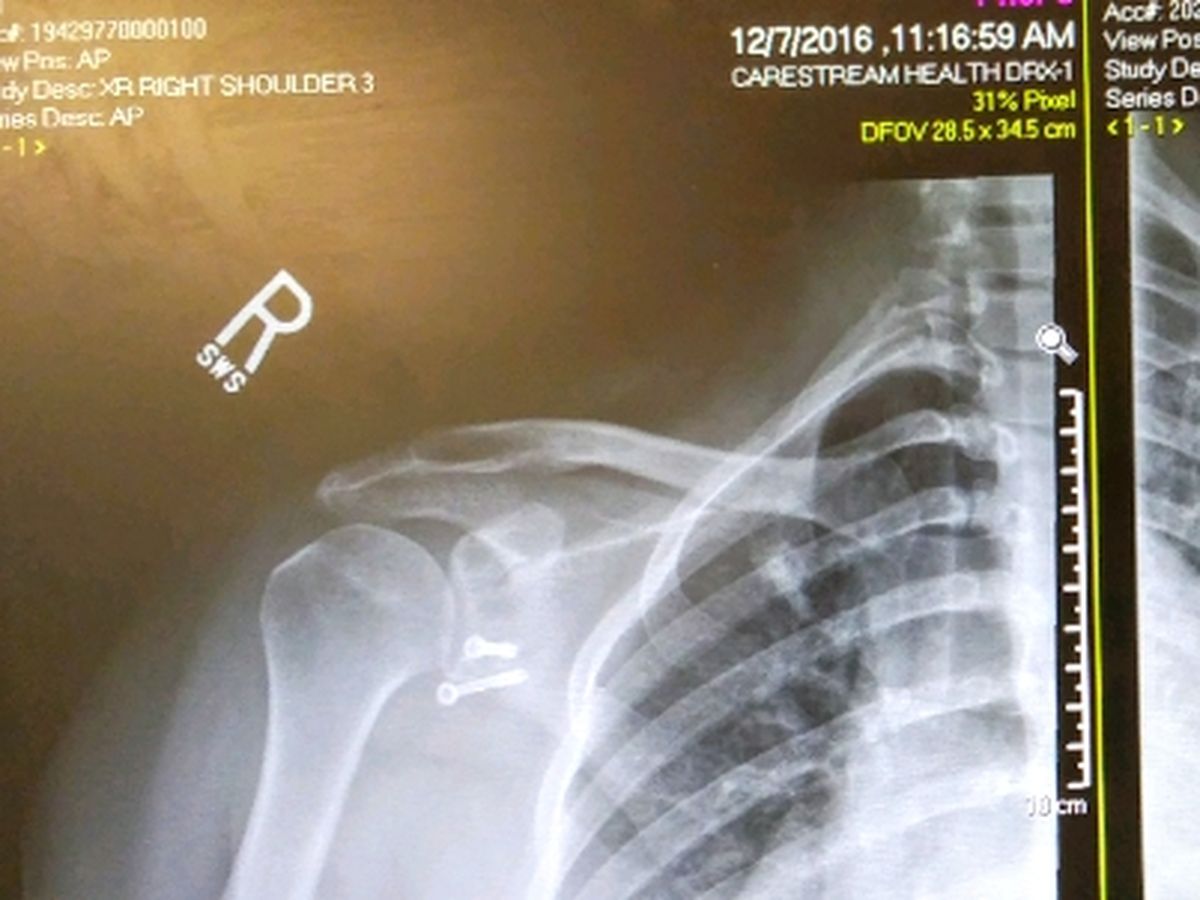

How does it affect me? My EDS manefested as gut issues my senior year of high school (07/08) and from then on my body seemed like it took a nose dive towards destruction. By the time I entered my twenties my body had started to completely fall apart. Starting with my shoulders spontaneously dislocating. The right one has done it so many times that I have had 2 major surgeries to repair the damage, and thanks to faulty connective tissue, both surgeries failed. So now I have a doner's tibia bone in my shoulder, two large metal screws, a ghastly scar, and an arm that tries to dislocate everytime I move it. And it's only a matter of time before the ligaments "naturally loosen up again and get so loose the cadaver bone no longer holds the joint in place" and the dislocations will begin again, according to my surgeon. It's gotten so painful I can no longer write, type, paint, color, or use my right arm in even basic ways without moderate to severe pain or numbness. And it's just a matter of time before it gets worse.